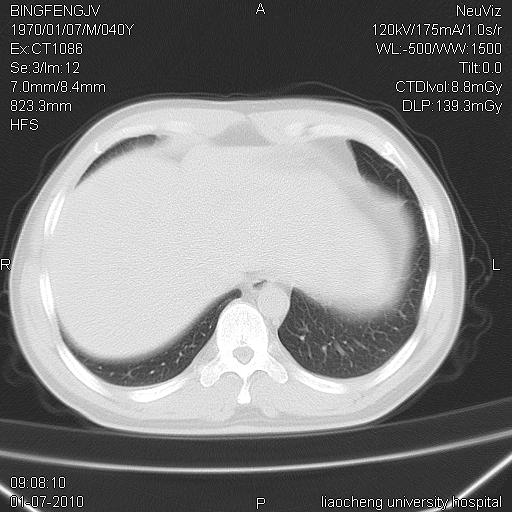

标题: CT23764B:男 40 肺部CT [打印本页]

标题: CT23764B:男 40 肺部CT

治疗2周后

考虑左肺上叶近胸膜下炎症并肺气囊形成。

炎症,大部吸收。